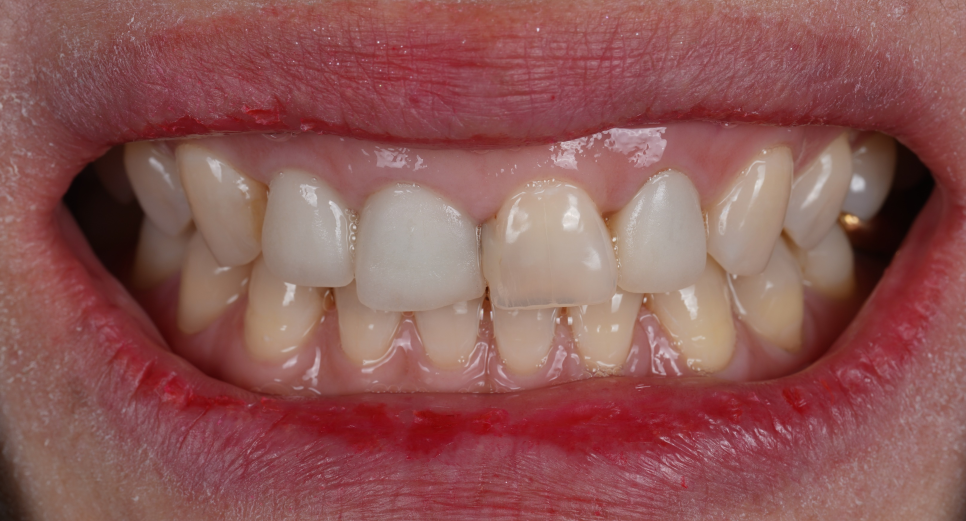

환자분께서는 웃을 때 잇몸이 많이 보이는 거미 스마일(Gummy Smile)을 개선하고 싶다고 하셨어요.

잇몸이 치아를 많이 덮고 있어서 송곳니부터 송곳니까지 6개 치아를 잇몸 성형하기로 했습니다.

잇몸성형 전, 후

251105 / 251117